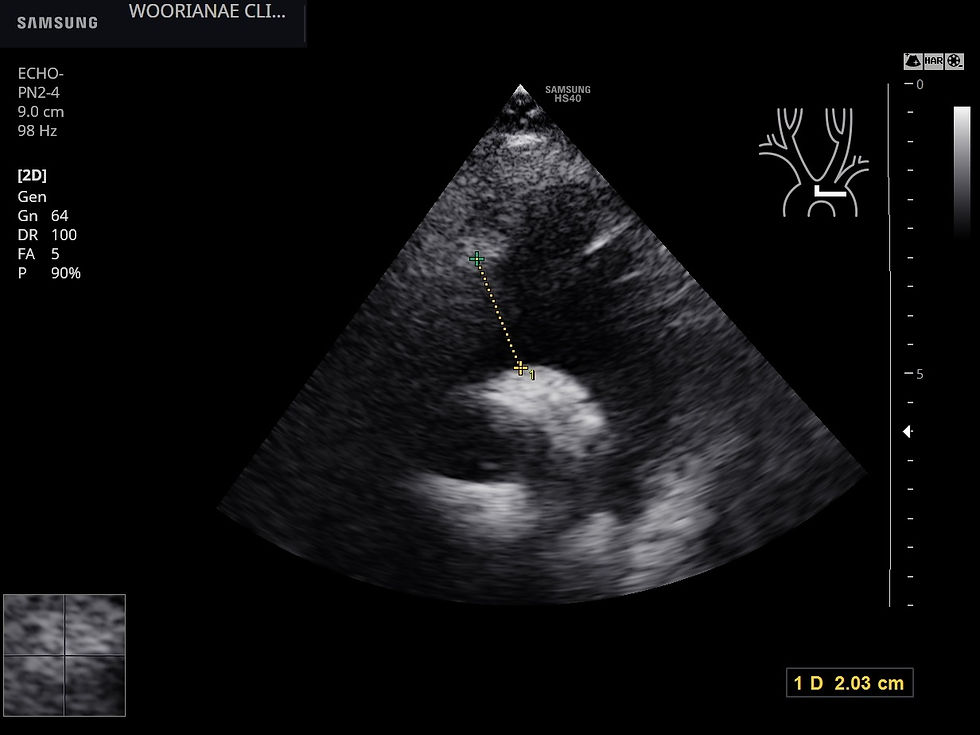

초음파 시행, sinus of valsava에서 대동맥 직경은 2.37 cm

z-score는 -2.0으로 평균을 크게 믿돈다. 따라서 음성

진단조건에 대동맥 직경이 z 값으로 2.0 이상이면서... 이므로 부합하지 않는다.